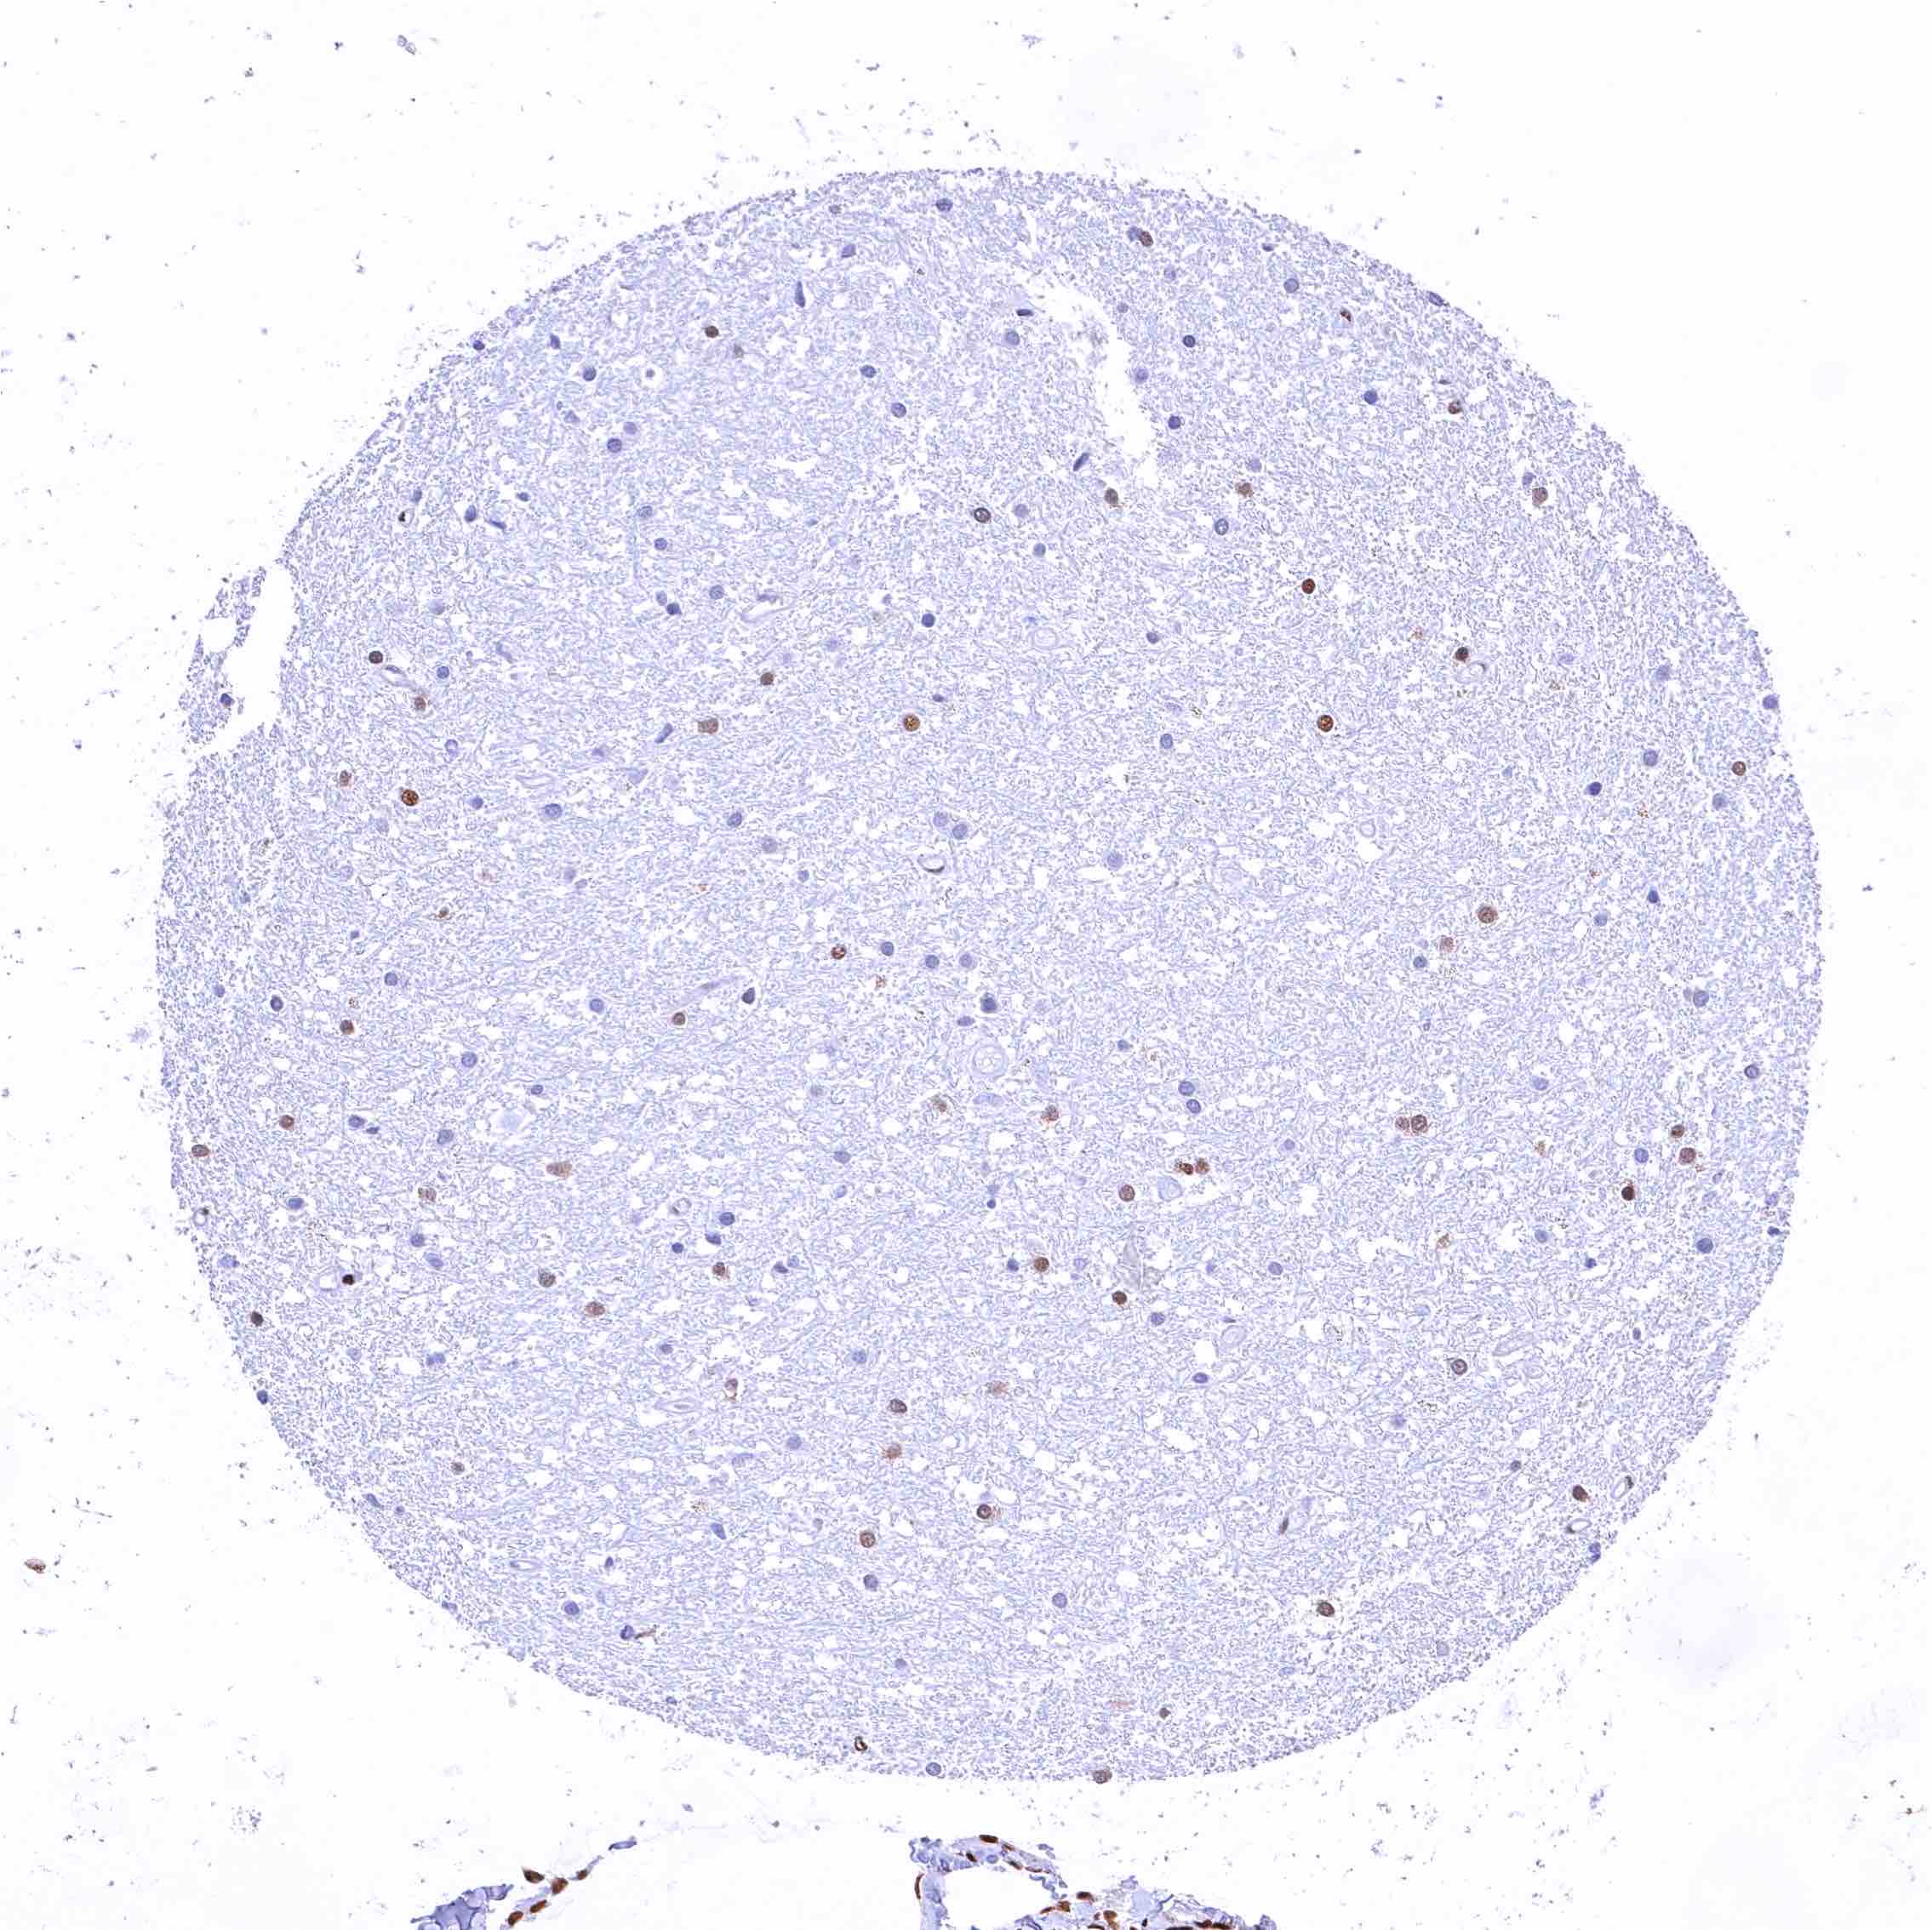

Cerebrum, grey matter – CBP staining is weak or absent in neuronal cells (weak staining may be related to prolonged fixation of ths sample)

Cerebrum, white matter – Weak staining may be related to prolonged fixation of ths sample